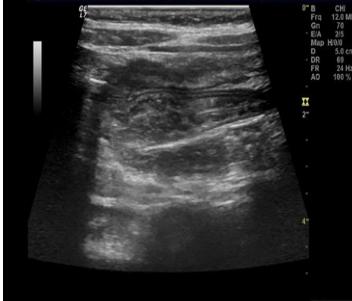

急性肠套叠是婴儿期的一种特有疾病,一岁以内多见,占60%~65%,其中又以4~10个月婴儿多见。2岁以后随年龄增长发病率逐年减少,5岁罕见。这是由于婴幼儿回盲部肠系膜尚未完全固定、活动度较大,因此容易出现肠套叠。根据调查显示,肠套叠的男婴发病率较高,男女孩的发病率之比约为2:1~3:1。肠套叠一年四季均有发病,以春季发病率较高,可能与上呼吸道感染及胃肠道病毒感染有关,夏冬次之,秋季较少见。临床排除肠套叠时,B超是首选。在B超下,肠套叠的部位可显示出边界清楚的包块。在肠管的横断面上呈现大环套小环的特征,即“同心圆征”。如下图所示。其表现为:外圆为均匀的低回声环带(系鞘部的肠壁回声),外圆内又有一个小低回声环带,形成内圆。内外圆之间为高回声环。形成“同心圆”。这可不是小虎队“爱”的魔力转圈圈后形成的哦。

肠套叠的同心圆症

换个角度来看TA的“侧脸”后,在专业人士的眼里中会更加直观。纵断面上侧呈现“假肾征”。这可不是因为“爱疯”换走了孩子的肾,这是心态“膨胀”后的肠管摆出来的独特POSE。

这种看起来像肾脏的“李鬼”在专业人士的眼中自然原形毕露啰